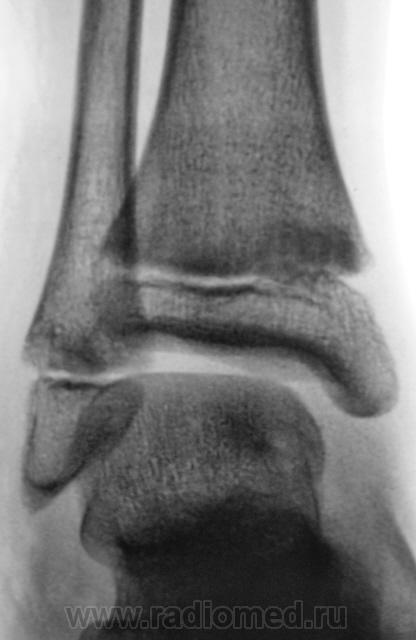

Уважаемый Валентин Львович! А что в жалобах, анамнезе? В переднемедиальной зоне дист. метафиза б/берцовой кости субхондрально под зоной роста участок уплотнения к/структуры, не отграниченный от неизмененной костн. ткани. Возможно, это импрессионный перелом? или остеонекроз? Смущает небольшой очаг аналогичной структуры в таранной кости под медиальным валом блока.

Согласен с коллегой helenmar по поводу перелома по типу импрессии, а ещё подвывих стопы в г/стопном суставе.

А как же объяснить асимметрию рентгеновской суставной щели?

А на мой взгляд, суставная щель вполне симметрична.

А, что, это за фрагментик?

1.Fragent.JPG2.Fragent.JPG3.Fragent.JPG

У взрослого такие соотношения в суставе назову супинационным подвывихом, хотя прямая проекция не оптимальна для такого заключения, боковая вовсе косая.